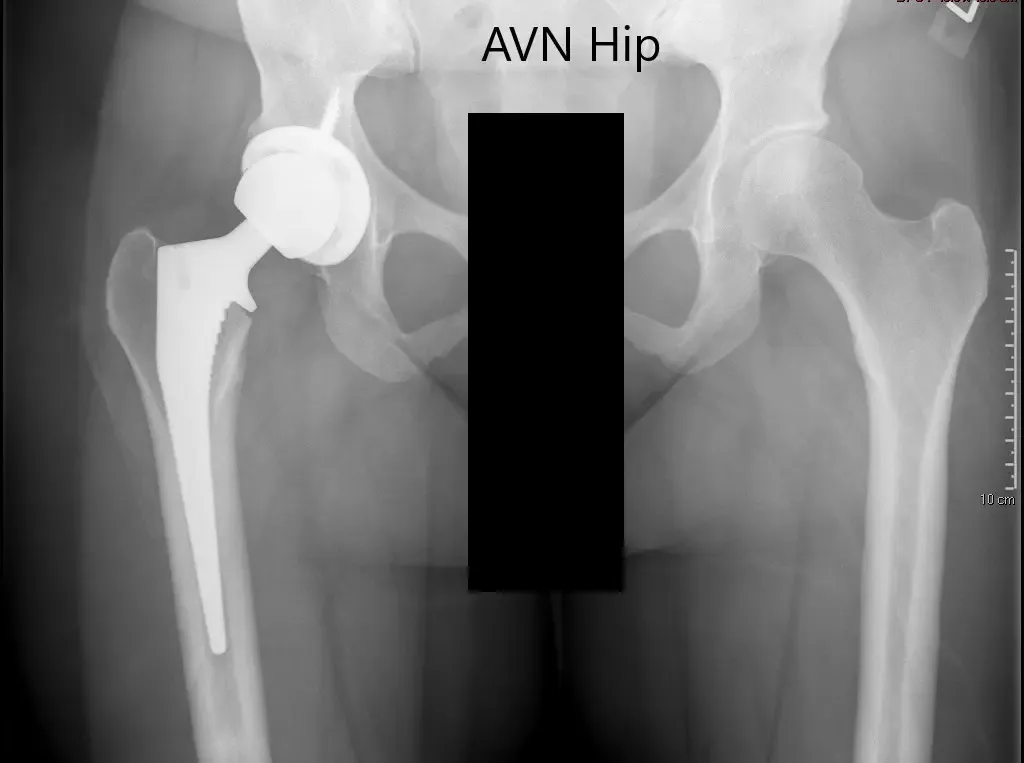

An X-ray was obtained which suggested a normal artificial joint on the right side. The left hip suggested some sclerosis with an intact spherical head of the femur. There was no crescent sign or any collapse.

Preoperative X-ray of the pelvis with both hips showing intact artificial joint on the right side and AVN of the left hip.